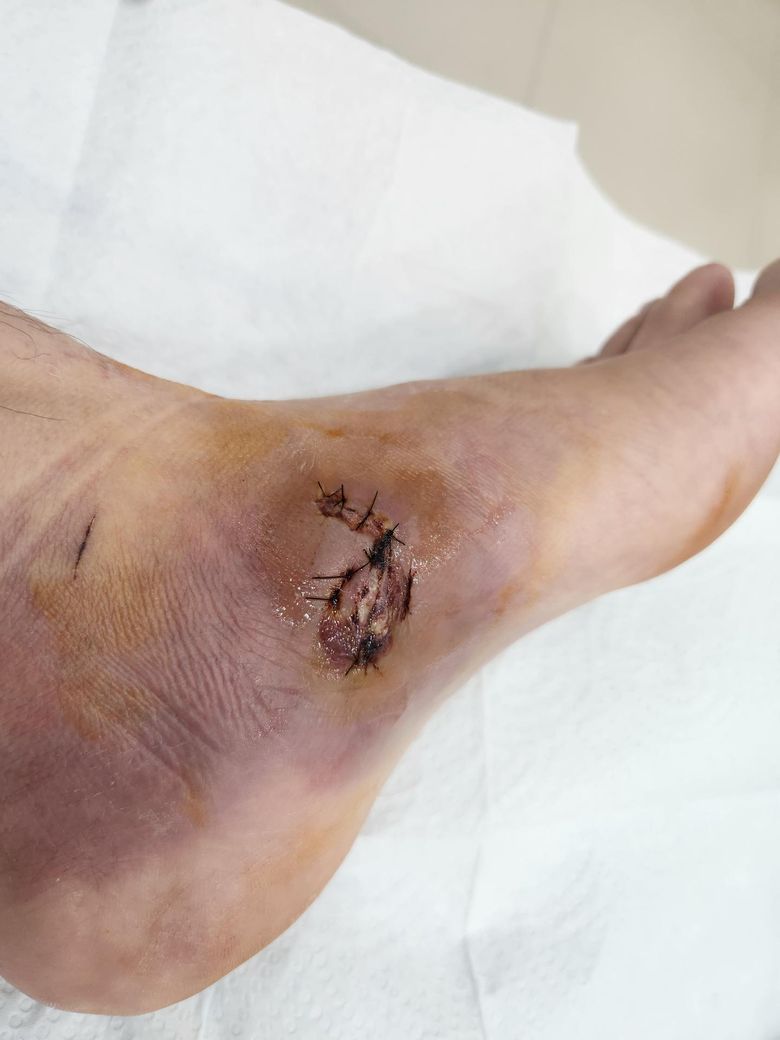

지금 10일차 상태인데 염증이 심한 편인가요? 이틀전에 봉합사가 일부 터져서 2바늘정도 재봉합했습니다. 우선 병원에서 입원이 필요하다고 해서 입원하려고 합니다

• 사진상 발 측면 열상 봉합 10일 경과 상처로 보이며, 현재 상태는 단순한 정상 치유 과정만으로 보기는 어렵습니다. 상처 중심부에 황백색 조직(삼출물 또는 괴사조직 가능성)이 보이고 봉합선 일부가 벌어진 흔적이 있으며, 주변 피부에 습윤과 변색이 있습니다. 특히 발은 보행으로 장력이 많이 걸리는 부위라 봉합부 벌어짐(dehiscence)과 감염 위험이 높은 부위입니다.

임상적으로 보면 현재 의심되는 상황은 다음 세 가지입니다.

첫째, 상처 부분 열개. 이미 봉합사 일부가 터져 재봉합을 한 점으로 보아 조직 장력이 계속 작용한 상태입니다.

둘째, 국소 감염 가능성. 황색 삼출물과 습윤 소견이 있어 세균 감염 가능성을 완전히 배제하기 어렵습니다. 다만 사진만으로 농성 감염인지 단순 섬유소 침착인지 구분은 제한적입니다.

셋째, 조직 괴사 또는 지연 치유. 발 측면은 혈류가 상대적으로 제한되고 보행으로 지속적 미세손상이 발생해 치유 지연이 흔합니다.

입원을 권유받은 것은 비교적 합리적인 판단으로 보입니다. 보통 이런 경우에는 상처 세척 및 괴사조직 제거, 정맥 항생제 투여, 보행 제한 및 드레싱 관리가 필요할 수 있습니다. 발 상처는 감염이 진행되면 피하조직염(cellulitis)이나 드물게 근막염까지 진행할 수 있어 초기에 적극적으로 관리하는 것이 중요합니다.

종합적으로 보면 현재 사진은 “정상적인 봉합 상처”라고 보기는 어렵고, 지연 치유 또는 초기 감염 가능성이 있어 입원 후 관리가 타당한 상태로 판단됩니다.

사진상으로는 "수술 부위 주변에 붓기와 멍이 있고 상처 중앙에 약간의 삼출물(노란 조직)"이 보여 관리가 필요한

상태로 보입니다.

특히 "봉합사가 일부 터져 재봉합까지 했다면 상처 벌어짐이나 감염 위험"을 주의해야 합니다.

올려주신 사진을 상세히 살펴 보았습니다. 올려주신 사진상 봉합 부위의 결손이 관찰되고 있어 약물 치료와 소독에도 호전이 없다면 추후 일부 피부 이식을 고려해야 할 것으로 보입니다. 입원 치료를 권유 받았다면 입원하여 치료를 하시면서 경과를 확인하는 것을 권해드립니다.